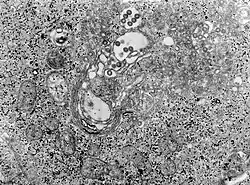

micrografía MET de tejido infectado con el virus de la fiebre del valle del Rift | ||